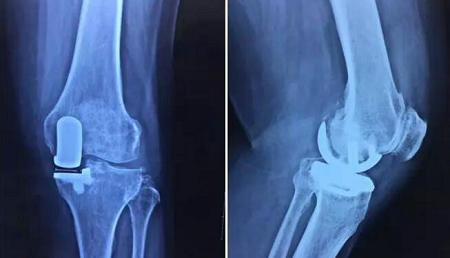

经过严谨的术前准备,邱东新医生手术小组顺利完成王老师的左膝关节单髁置换手术,仅花了1.5小时。手术中,邱医生对王老师膝关节内自身所有结构都不做任何的破坏,精确测量假体,安放试模后,屈伸活动关节,内外侧平衡良好,髌骨轨迹良好,下肢力线良好,安放胫骨假体,检查关节稳定,手术成功完成。